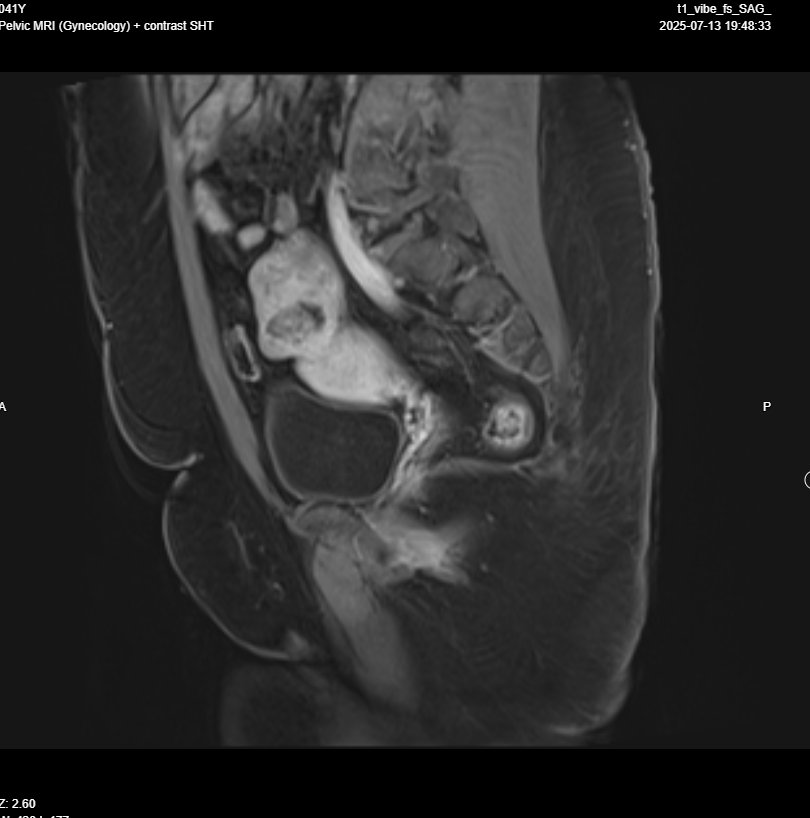

Pelvic MRI with IV contrast

· Evidence of left adnexal irregular lobulated shape solid mass replacing most of left ovarian parenchyma , T1 iso intense , T2 hypo intense , restricted in DWI, no fat , no calcification , after giving contrast showing diffuse progressive hyper enhancement , with high risk curve of enhancement , these radiological features highly suspicious for malignant ovarian tumor, O-RADS 5.